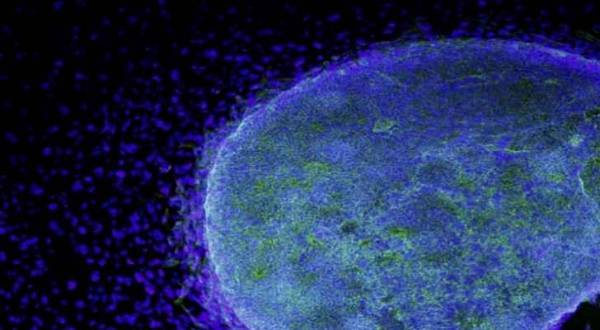

أخبار البلد -   أخبار البلد - نجح الباحثون في إنشاء غدة التوتة الاصطناعية القادرة على قتل مسببات الأمراض المسؤولة عن نمو الأورام السرطانية.

ويستخدم الجهاز الاصطناعي الخلايا الجذعية في الدم لإنشاء "غدة اصطناعية" قادرة على إنتاج خلايا تائية متخصصة، يمكنها الكشف عن نطاق واسع من الفيروسات، على غرار عمل الخلايا الطبيعية.